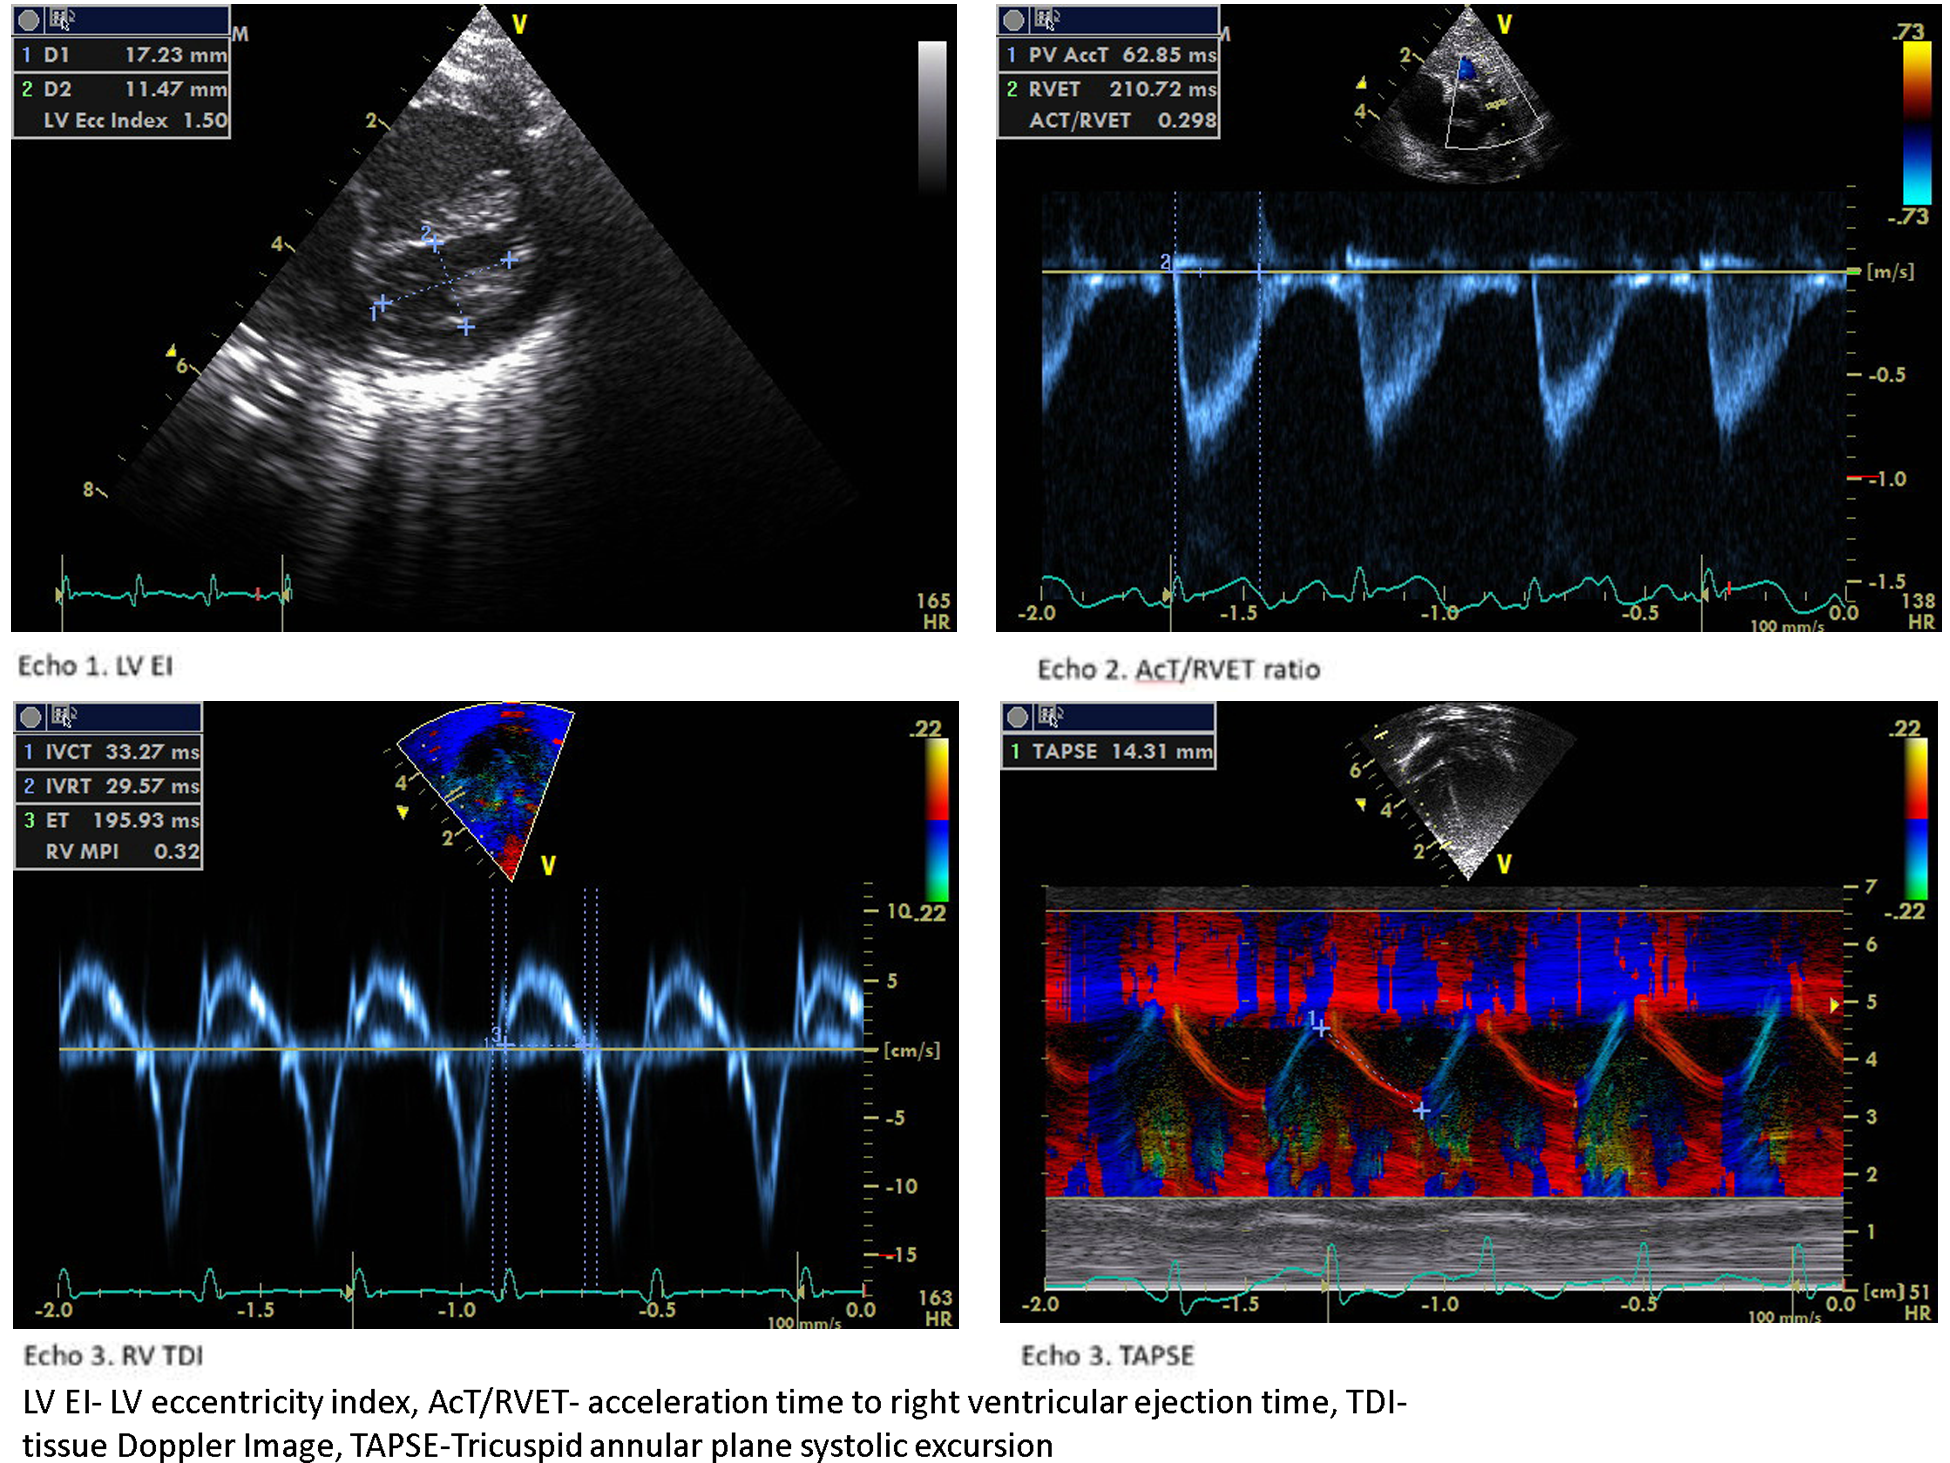

The LV EI is an objective measure of septal configuration at a modified short-axis view (Figure 1, echo) and is a useful marker of RV systolic hypertension (26). In our study, LVEI, ACT/RVET, and basal RV dimensions were statistically significantly different from 33 weeks onwards. Abraham and Weismann showed LV EI >1.15 correlates with systolic septal flattening and a ratio >1.3 was associated with RV functional impairment (14). The utility of age-dependent LV EI and cut-off values in predicting PH has also been validated by Schweintzger et al. (27). Our study showed an end-systolic LV EI >1.16 had high sensitivity and specificity in diagnosing BPD-PH.

The ACT/RVET has been correlated with catheter-measured pulmonary pressure (28). The lower ratio <0.31 reliably detected elevated pulmonary vascular resistance with high sensitivity and specificity in older children (9, 29). In our study, the BPD-PH group had a lower ratio (<25) but had lower sensitivity and specificity. Nonetheless, this is a simple cardiac parameter that can be used in conjunction with other cardiac parameters in the diagnosis of BPD-PH. The ACT time was not significant between the two cohorts in our study. ACT is known to be shorter in neonates due to the faster heart rate and is well validated in older children with PH (30).

We observed a decreased RV E’ and E/E’, a marker of diastolic dysfunction in the BPD-PH group, but the difference was not statistically significant. The myocardial performance (Tei) index is a measure of global ventricular function (43). Patel et al. showed significantly higher RV MPI in infants with PH but a poor correlation with pulmonary artery pressure measured by TR (44). We found that RV MPI had a high predictive value followed by IVRT and IVCT. To the best of our knowledge, this is the first study to show the serial RV functional assessment in the evolution of BPD-PH. Figure 4 shows the sample 2D echocardiogram images of various conventional and TDI images from the study.

Figure 4

Echocardiogram images of the study population.